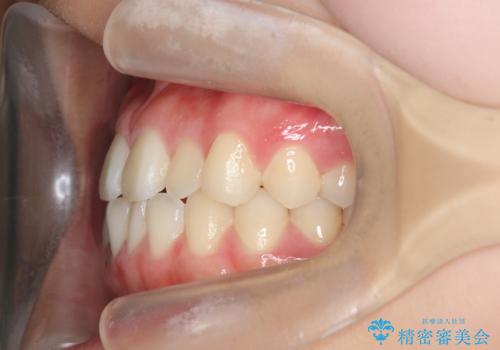

マウスピース矯正で前歯のガタつきを改善

- 上下の前歯のガタつきの改善を求めて、矯正治療を希望され来院されました。

矯正検査の結果、マウスピース矯正システム インビザラインの適応であることからワイヤーを用いず矯正治療を進めることとしました。

1日20時間以上の使用時間をきっちりと守っていただけたため、良好な治療結果、歯並びを手に入れることができました。